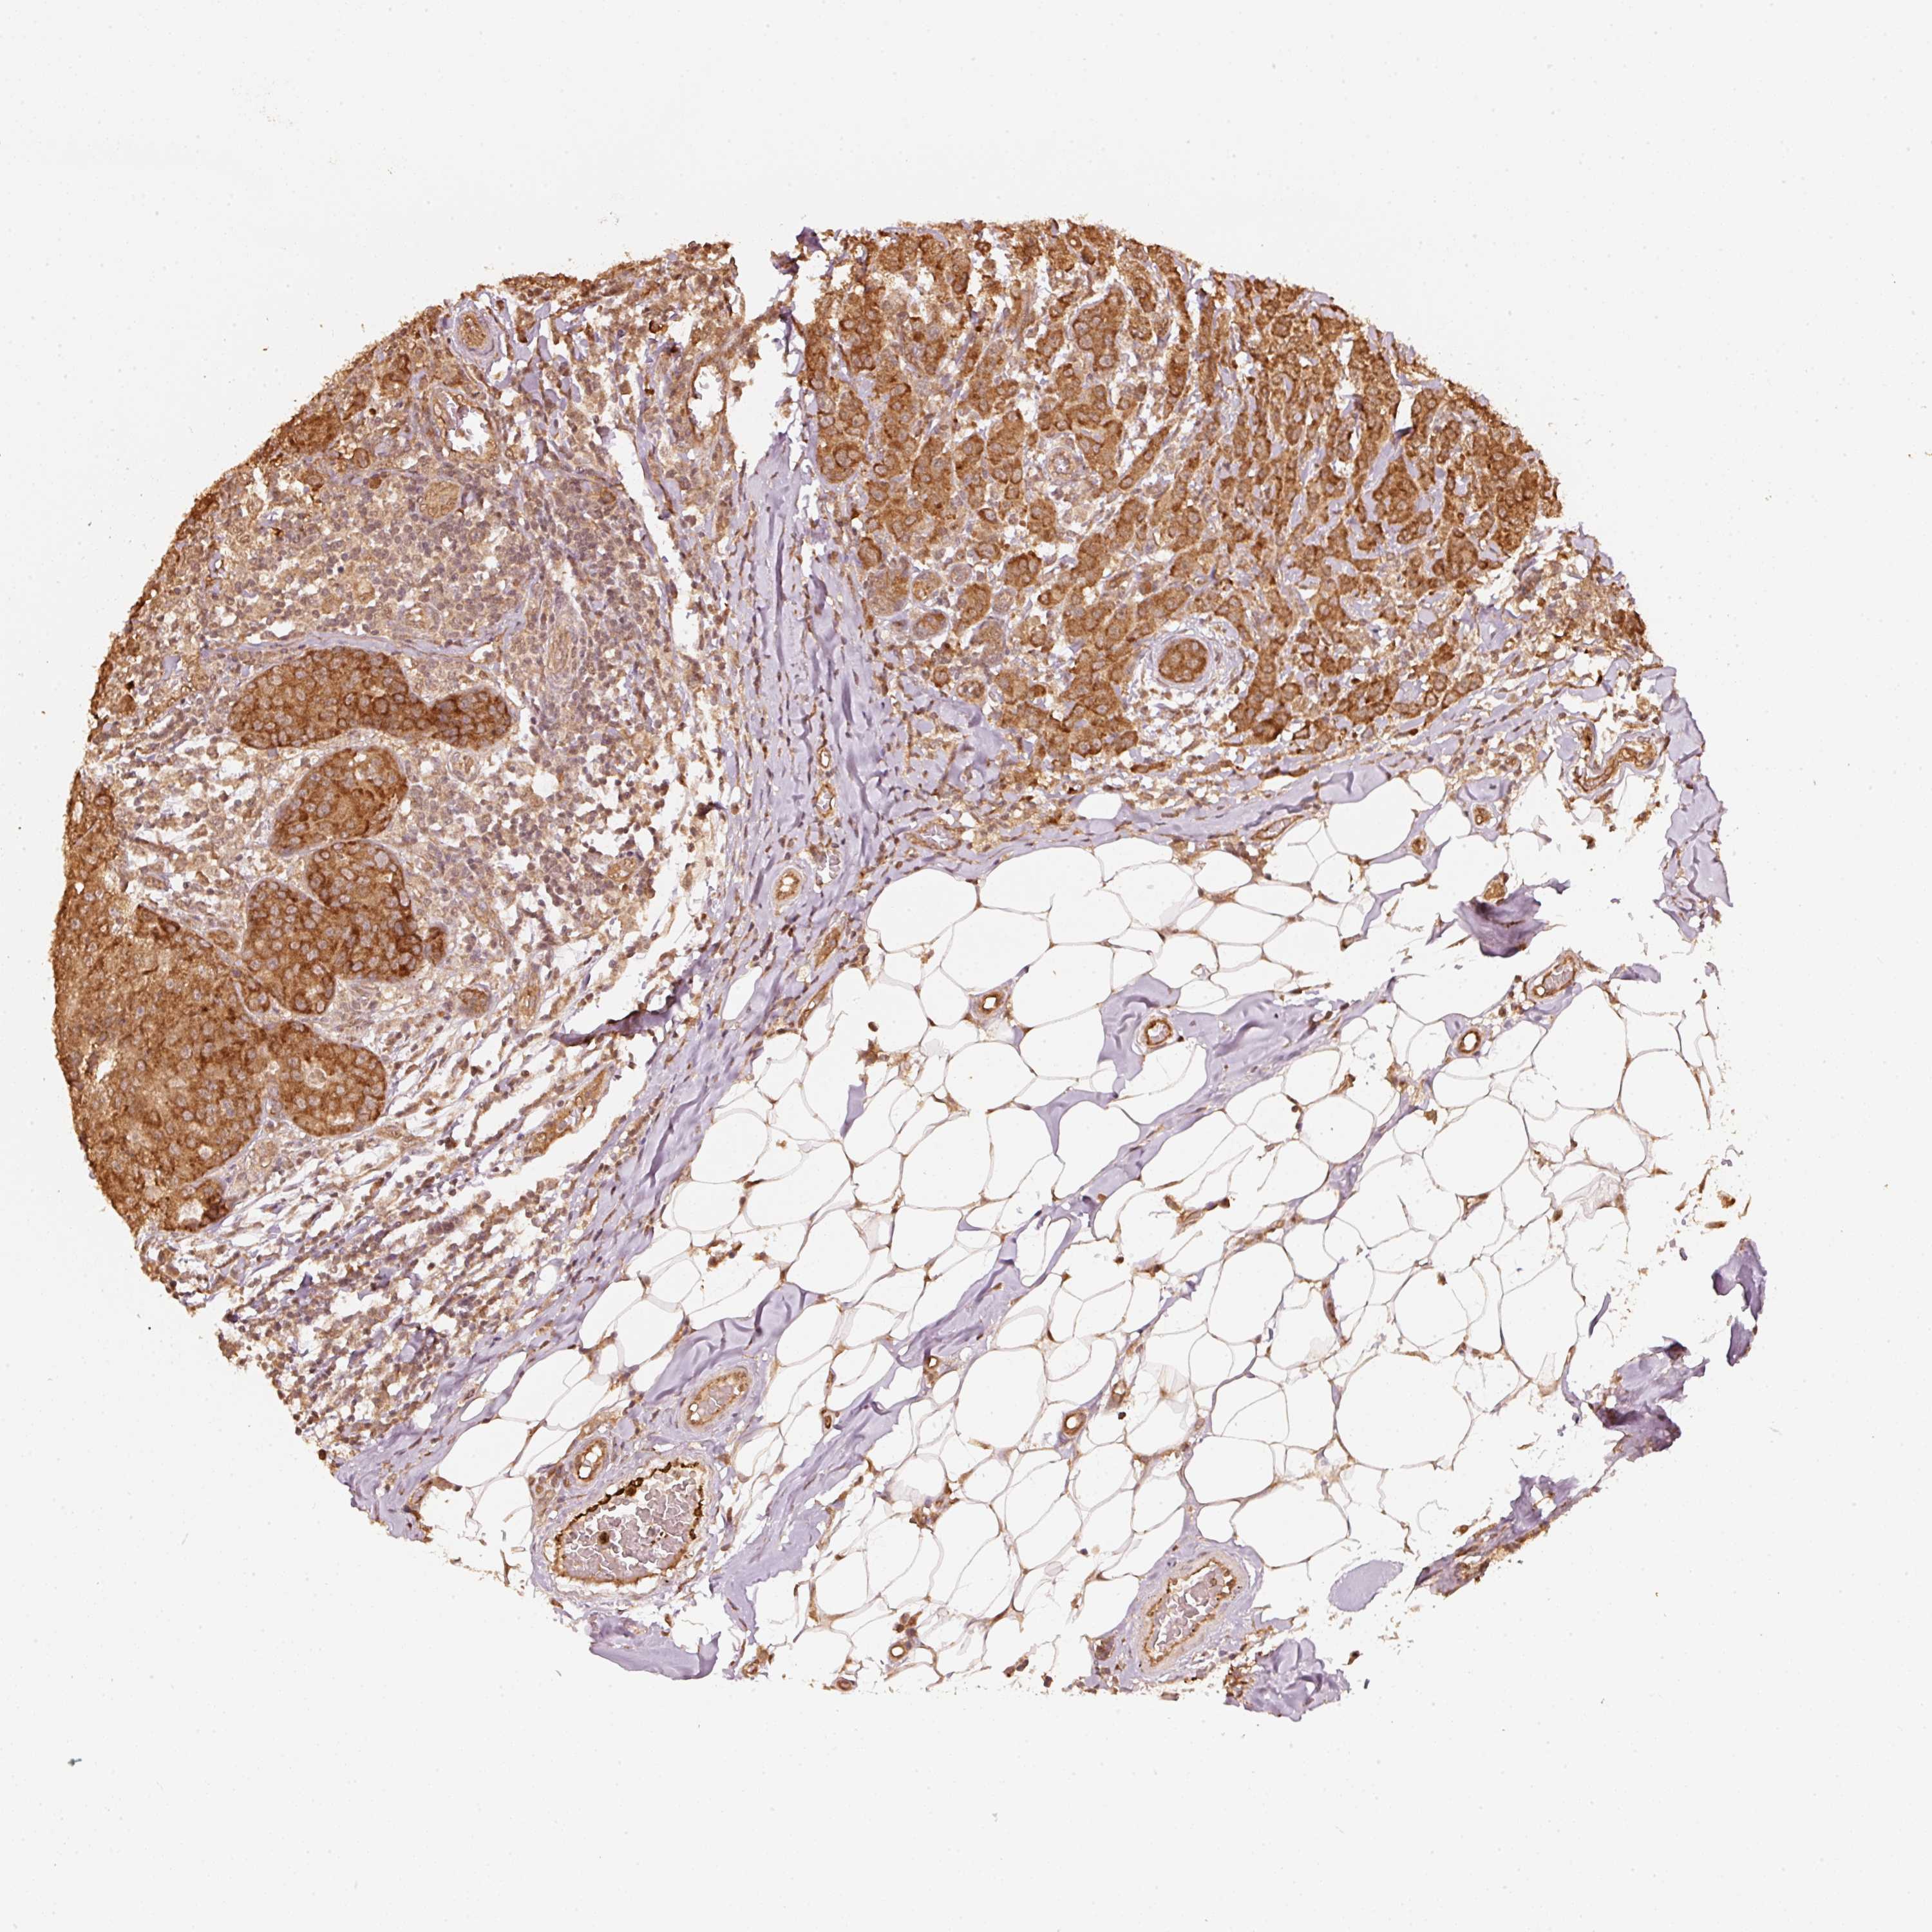

CANCER BREAST CANCER Show tissue menu

BRCA TCGA BRCA VALIDATION PROTEIN EXPRESSION